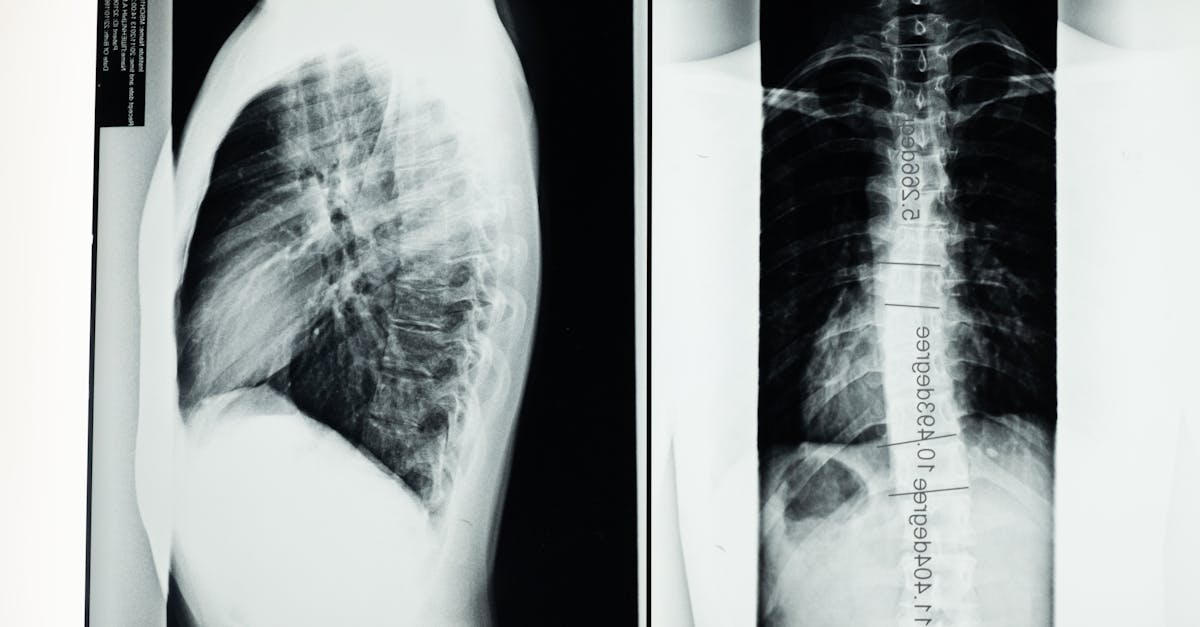

Des examens complémentaires, tels que des radiographies, IRM ou scanners, sont souvent requis. Ces outils d’imagerie permettent d’observer en profondeur les structures vertébrales et d’identifier les anomalies telles que les hernies discales ou les rétrécissements du canal rachidien. Les résultats aident à affiner le diagnostic.

Étape 3 : Examens complémentaires

Lorsqu’il est nécessaire, des examens complémentaires tels que des radiographies, des IRM ou des scanners peuvent être recommandés. Ces outils d’imagerie permettent d’obtenir une vision plus précise des structures vertébrales, d’évaluer l’état des disques intervertébraux et de détecter d’éventuelles anomalies comme des hernies discales ou des sténoses foraminales. Ces résultats serviront à confirmer le diagnostic initial et à élaborer un plan de traitement adapté.

| Diagnostic par imagerie | Utiliser des radiographies, IRM ou scanners pour visualiser les problèmes vertébraux. |

Pour compléter les premières étapes, des examens d’imagerie peuvent être requis. Ces examens, tels que la radiographie, l’IRM ou le scanner, permettent d’obtenir une visualisation interne des structures vertébrales et des tissus adjacents. Ils fournissent des indications essentielles sur la santé des disques intervertébraux, la présence de hernies discales, de protrusions ou d’autres anomalies qui peuvent contribuer aux douleurs ressenties par le patient.

Enfin, il ne faut pas négliger l’importance des examens complémentaires, tels que les analyses d’imageries (IRM, scanner) qui offrent une vue détaillée des structures vertébrales. Ces outils de diagnostic permettent de visualiser les lésions et de confirmer ou d’infirmer les hypothèses posées lors des étapes précédentes.